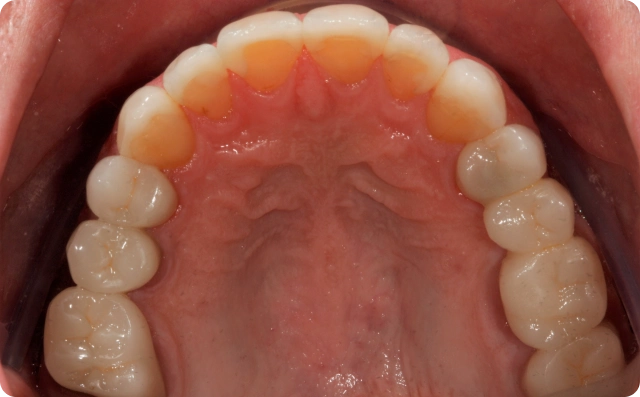

Depois

Foram confeccionadas facetas cerâmicas de dentes caninos a caninos superiores e inferiores, ponte fixa na região superior direita e coroas unitárias em dissilicato de lítio nos pré molares e molares.